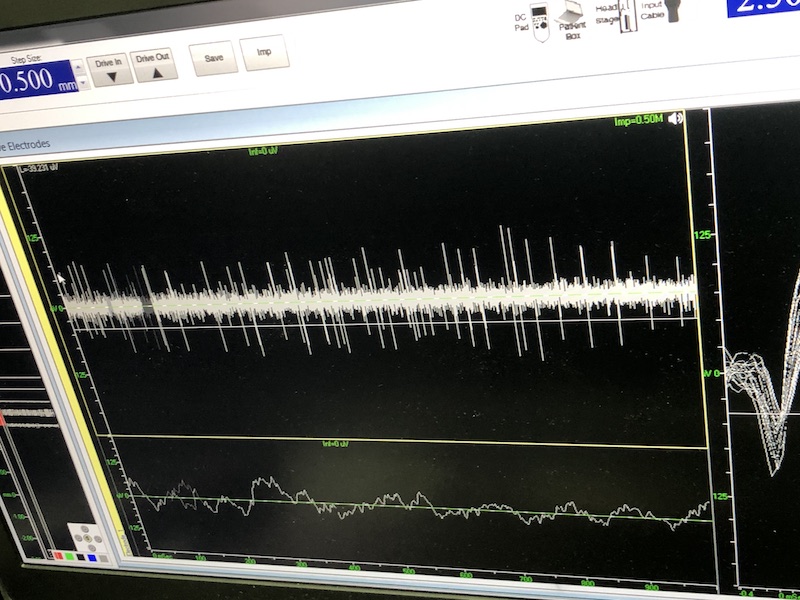

與此同時(shí),檢測電極實(shí)時(shí)記錄電極末端每一點(diǎn)處的電信號(hào),當(dāng)電極逐漸接近手術(shù)規(guī)劃靶點(diǎn)時(shí),借助電信號(hào)的特征,醫(yī)生可以判斷電極是否已經(jīng)沿長軸植入患者顱內(nèi)的目標(biāo)核團(tuán),以及植入的準(zhǔn)確長度。下圖中,檢測信號(hào)屬于典型的核團(tuán)信號(hào),證明電極已經(jīng)抵達(dá)相對(duì)理想的植入位置,記錄下此刻的位置后,即可在相應(yīng)位置植入刺激電極。

檢測核團(tuán)信號(hào)